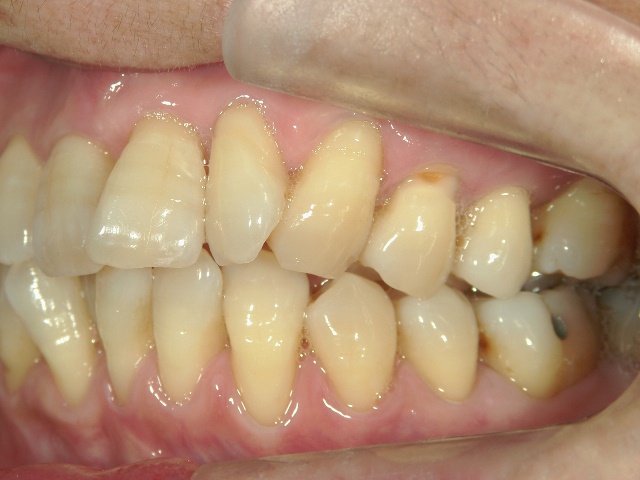

矯正歯科 治療後矯正歯科 プチワイヤー矯正 治療後矯正歯科(プチワイヤー矯正)治療後

矯正歯科 治療後

no.12_5333_治療後_左.jpgno.12_5333_治療後_正面.jpgno.12_5333_治療後_右.jpg